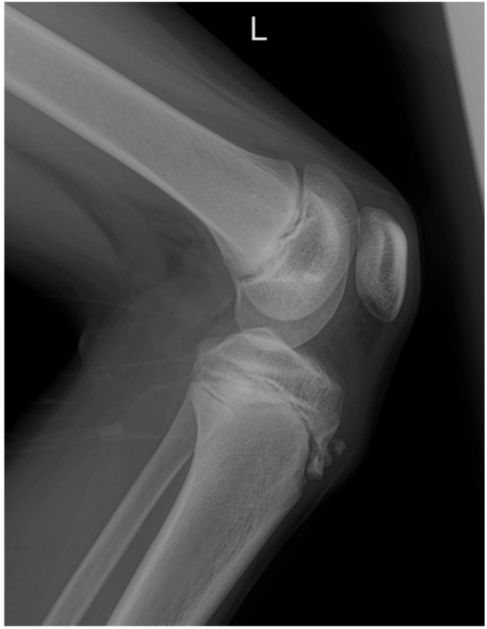

Criança de 12 anos de idade comparece ao pronto-atendimento queixando-se de dor intensa em região anterior do joelho, na topografia da tuberosidade tibial. Realizada radiografia em perfil do joelho.

Figura 2 –Radiografia em perfil do joelho.

Enunciado 4478611-1

Fonte: CPCON.

Com relação ao provável diagnóstico, assinale a alternativaCORRETA.